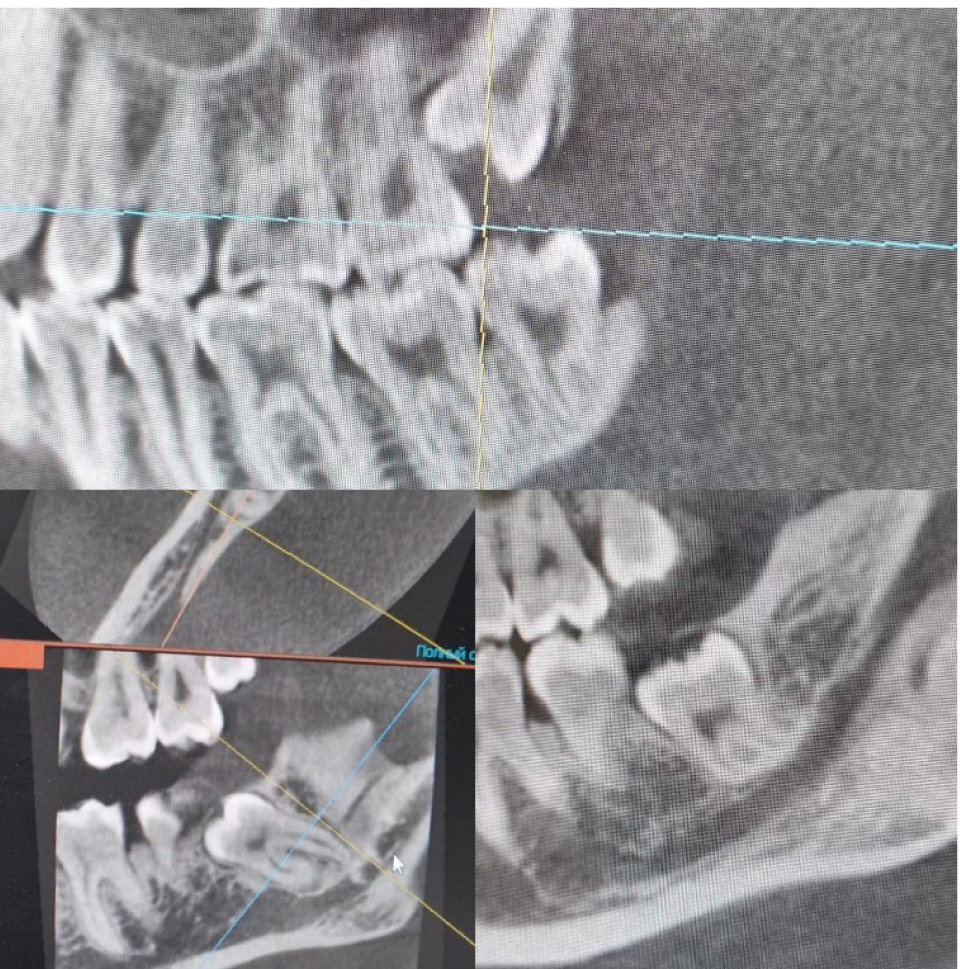

Всем пациентам проведено обследование, составлен план лечения. Операция атипичного удаления проводилась максимально щадящим способом с отслаиванием слизисто-надкостничного лоскута, трепанацией кортикальной пластинки костной и фрагментацией удаляемого зуба. Операционная рана заполнялась остеопластическим материалом, слизисто-надкостничный лоскут укладывался на место, накладывались узловые швы синтетическим, монофиламентым шовным материалом (рис. 4).

Рис. 4. Состояние лунок удаленных ретинированных зубов